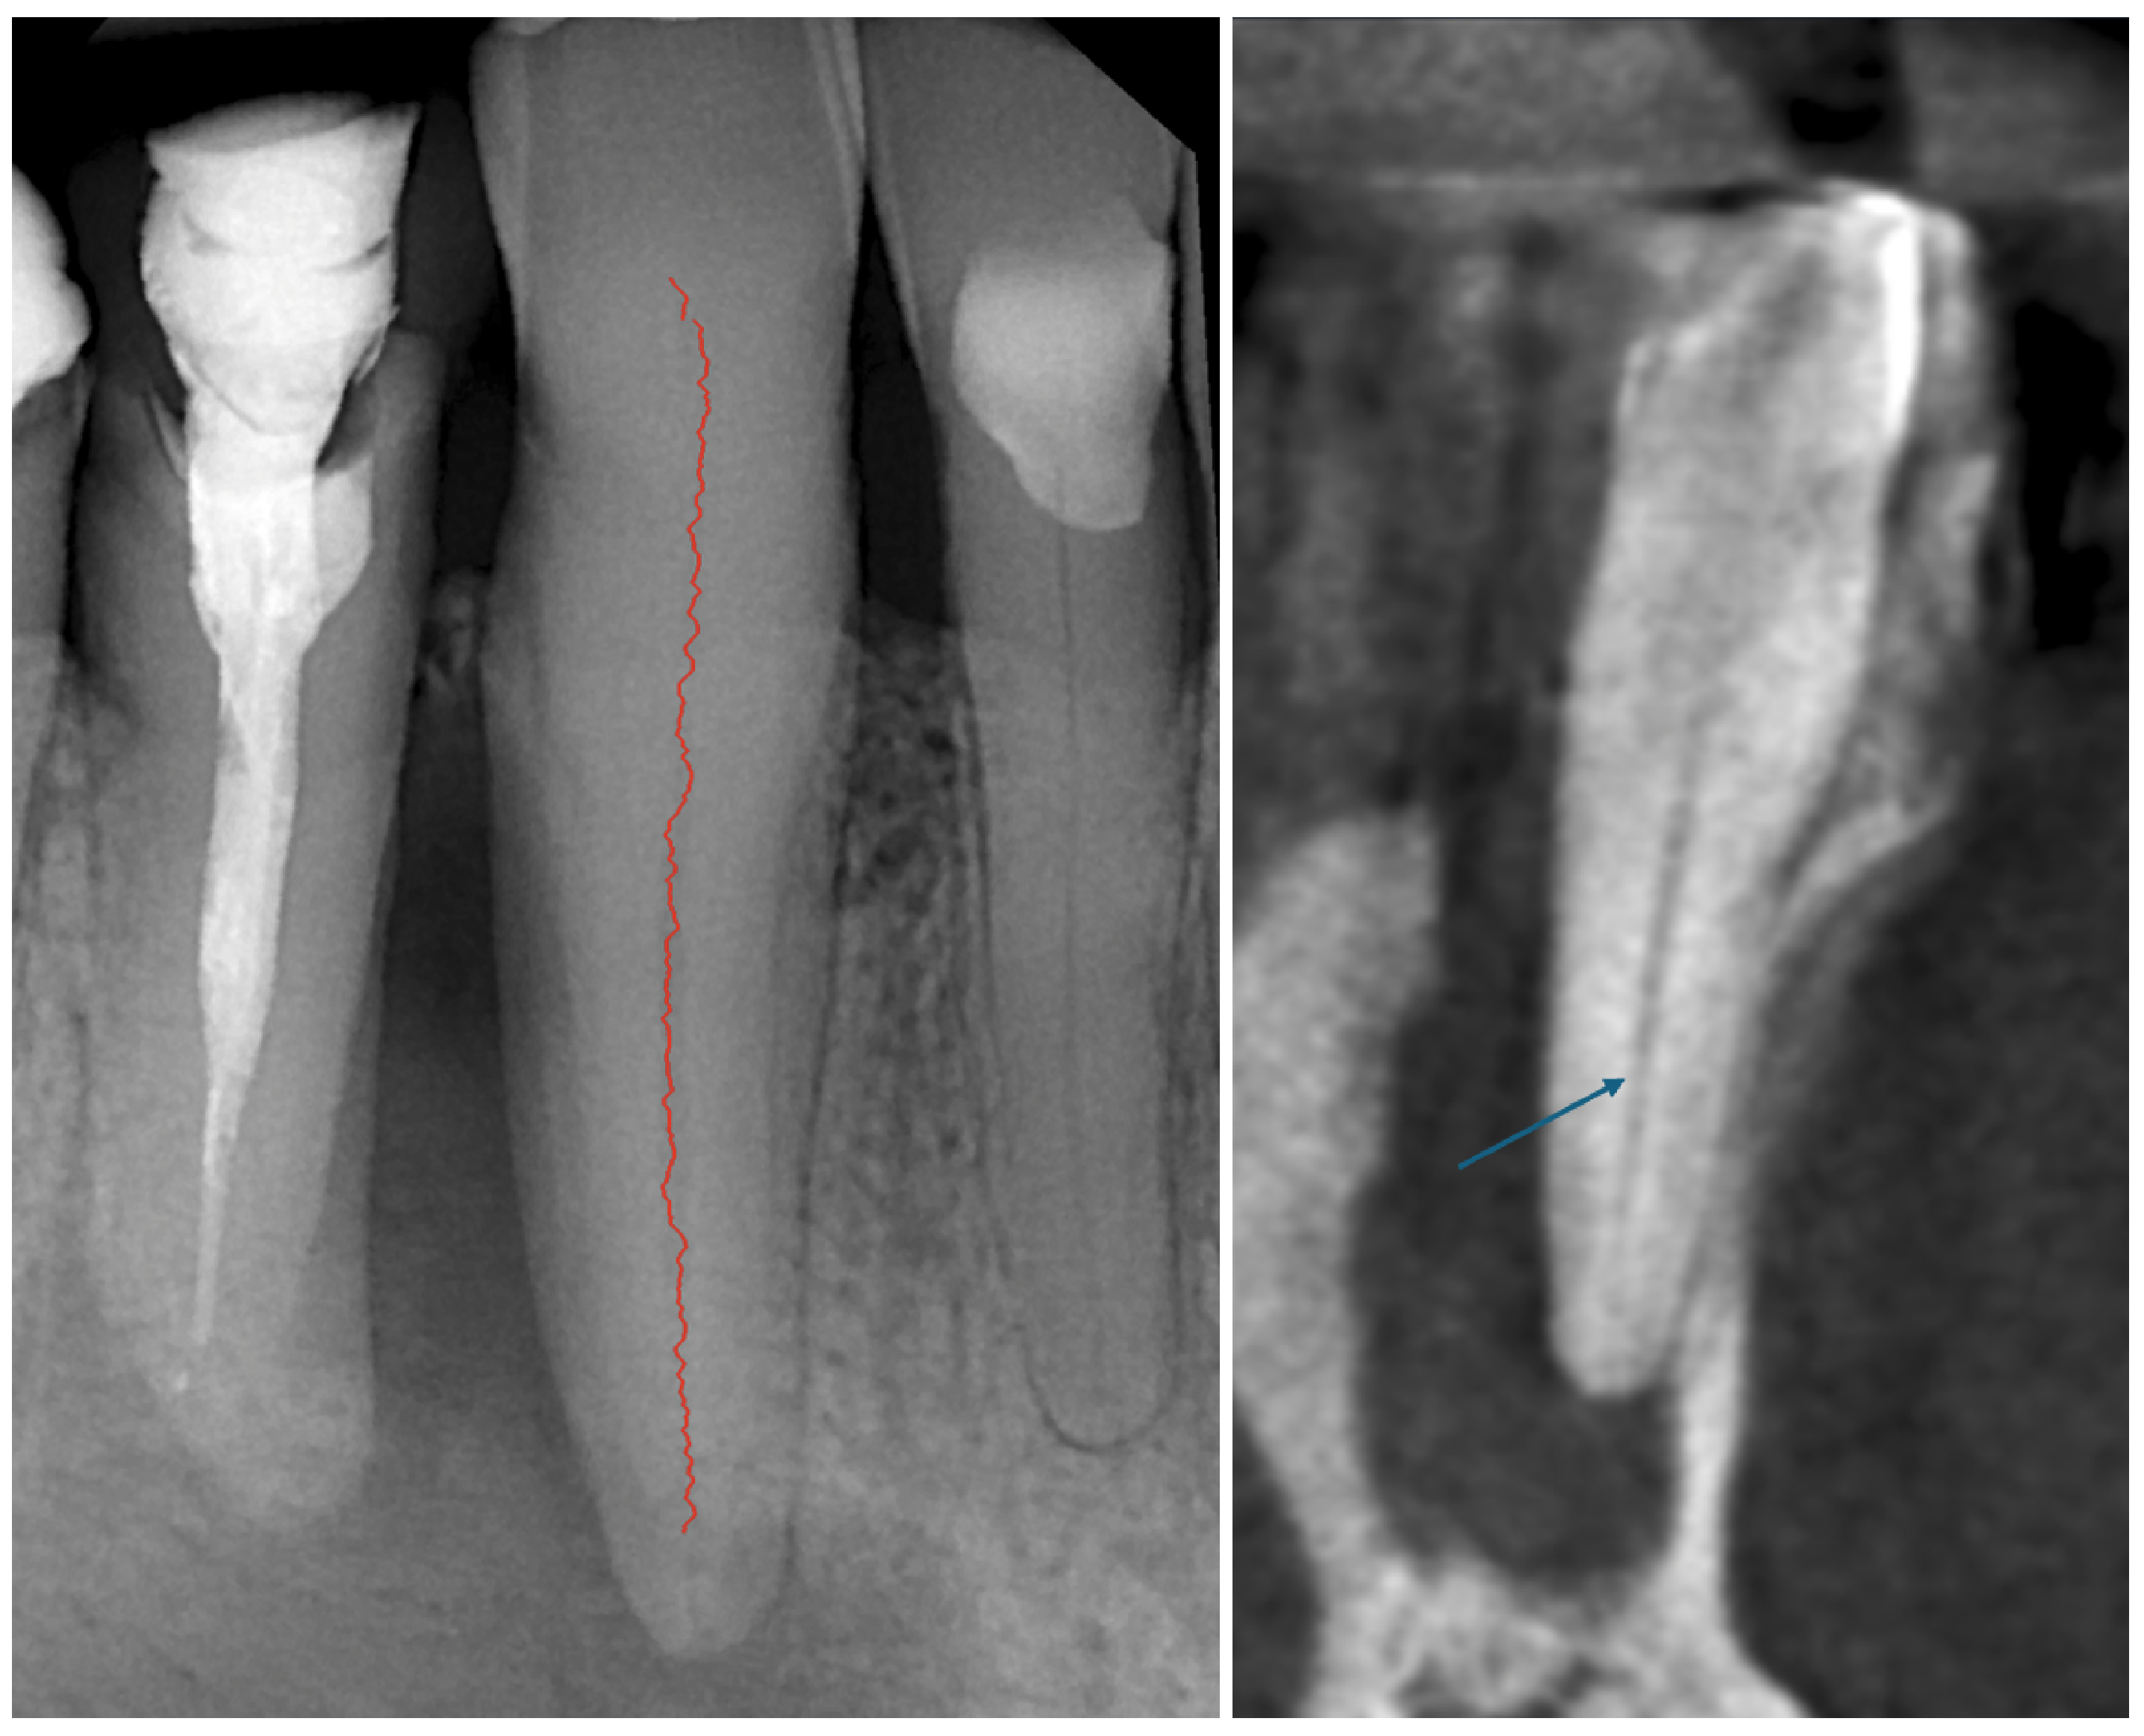

Root Canal Detection on Endodontic Radiographs with Use of Viterbi Algorithm